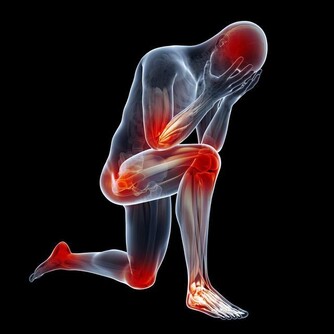

問題三:老年癡呆會不會遺傳?

研究證明,阿爾茨海默病患者大部分是散發,但是部分有家庭聚集的傾向。目前已經明確與阿爾茨海默病相關的基因有四對,分別為APP、PS1、PS2、APOE4基因。

如果家庭有好幾個,或者有好幾代人患病,就提倡做檢測。當然,攜帶高危基因,也不一定患病,還要看後天環境。

此外,需要注意的是,這4類指標出現異常的人,容易得老年癡呆:同型半胱氨酸、甲狀腺功能、血糖、血脂。